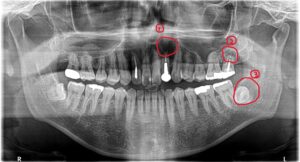

患者さんは50代男性。左上前歯の歯茎から膿が出るのを主訴に来院されました。

パノラマ撮影を行うと…

3つの大きな嚢胞が映ってきました(;゚Д゚)

①上顎左側側切歯根尖部に100円玉ぐらいの歯根嚢胞を認めます。

②上顎左側第二大臼歯根尖部に1円玉ぐらいの歯根嚢胞を認めます。

③下顎左側智歯周囲に500円玉くらいの含歯嚢胞を認めます。

※後日病理組織診断を行っております。